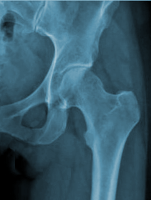

HANCHE - Articulation COXO-FEMORALE

Généralités

C'est une énarthrose (3 ddl) qui

unit la cuisse au bassin : l'os coxal (old.

os iliaque) à l'extrémité proximale du fémur

articulation transmet le poids du corps au membre inférieur.

Surfaces Articulaires

- En DH : sur le fémur, la tête fémorale représente les 2/3 d'une

sphère pleine (20 à 25 mm de rayon). Elle est recouverte de cartilage

(plus épais en HT qu'en BAS) à l'exception de la fovéa d'insertion du

ligament. Elle regarde en DD, en HT et en AV (15° par rapport au plan

frontal). La tête fémorale est reliée à la diaphyse par le "col du

fémur".

- En DD : sur la face externe de l'os coxal, dans son segment moyen,

au dessus du trou obturateur : l'acétabulum

(old. cavité cotyloïde). C'est une cavité hémisphérique limitée

dans son pourtour par un sourcil ou lèvre (plus marqué en HT) et par

l'échancrure ischio-pubienne en BAS. Elle présente 2 régions : à la

périphérie, une surface semi-lunaire encroûtée de cartilage (en forme

de croissant concave vers le BAS et se terminant par 2 cornes :

antérieure et postérieure) et au centre, la fosse acétabulaire

(old. arr. fond) non recouverte de cartilage, non articulaire

(remplie d'un paquet adipeux).

Avec

l'âge, c'est une articulation fréquemment atteinte d'arthrose

(coxarthrose). Le col du fémur devient fragile chez les personnes âgées

(femme ménopausée surtout car décalcification plus importante). La

luxation reste rare et entraîne souvent la fracture.

L'angle

cervico-diaphysaire entre la diaphyse et la tête passe de 140/145° chez

l'enfant à 125° chez l'adulte, puis à 120° chez le vieillard.